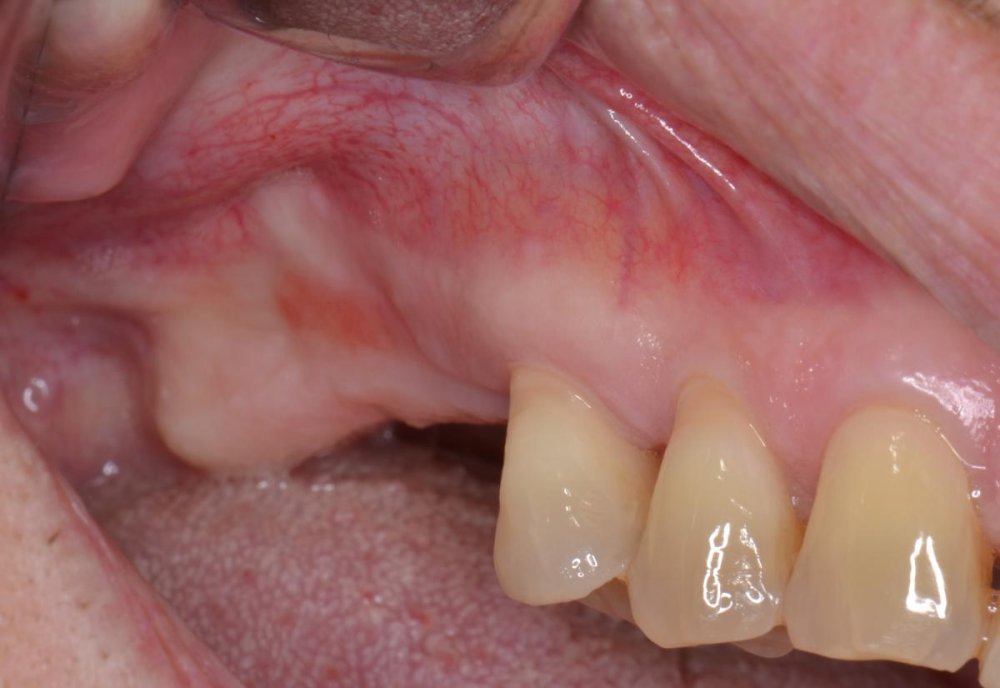

Ecco le immagini cliniche

post-729-0-73174000-1384250647_thumb.jpg

l' esame CBCT evidenzia un' immagine compatibile con pseudocisti antrale